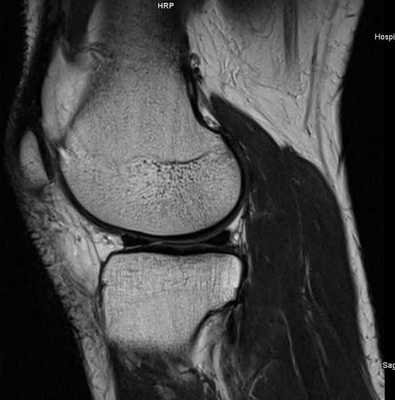

МР-скан коленного сустава в Т1 режиме (стрелкой указан костный отек)

При МРТ получают серии монохромных снимков анатомической области в аксиальной, сагиттальной и фронтальной плоскостях. При изучении изображений врач видит контуры различных элементов сочленения. Расшифровка МРТ-снимка коленного сустава подразумевает оценку сканов в сравнении с нормой. МР-томограммы называют срезами, поскольку изображения производят послойно, с шагом 1-2 мм. Врач последовательно изучает анатомическую зону на предмет соответствия всех структур норме. В процессе расшифровки фото обращают внимание на качество визуализации элементов, четкость контуров, присутствие зон измененного МР-сигнала (гипер- или гипоинтенсивного) в различных режимах сканирования (Т1 ВИ, Т2 ВИ, ДВИ, подавление жира).

МРТ коленного сустава.В норме на МР-томограмме коленного сустава хрящ (яркий) покрывающий суставную поверхность имеет равномерную толщину, суставная поверхность имеет ровную форму, возможно минимальное количество жидкости, мениск имеет гипоинтенсивный МР-сигнал. У молодых людей имеется гипернтенсивный сигнал в метаэпифизе — зона роста (яркий МР-сигнал).